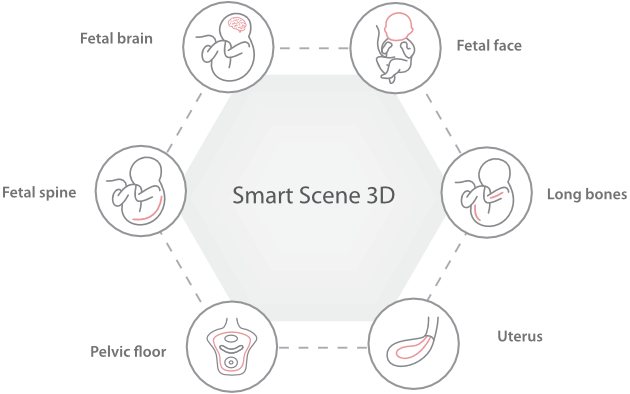

Le Nuewa?I9, con?u spÃĐcialement pour la santÃĐ de la femme et les soins nÃĐonataux, offre une expÃĐrience entiÃĻrement nouvelle gr?ce aux innovations dont il est dotÃĐ, tant à lâintÃĐrieur quâà lâextÃĐrieur. Ces innovations sont dÃĐveloppÃĐes sur la base d'une comprÃĐhension approfondie de scÃĐnarios cliniques complexes, fournissant des rÃĐponses prÃĐcises et adaptÃĐes ainsi qu'une efficacitÃĐ exceptionnelle et une expÃĐrience utilisateur remarquable.

La plate-forme ZST+?est une innovation extraordinaire, reprÃĐsentant une ÃĐvolution de lâimagerie ultrasonore. Elle transforme la formation conventionnelle de faisceaux en un traitement basÃĐ sur les canaux de donnÃĐes. Elle repousse les limites de lâimagerie conventionnelle et du compromis entre rÃĐsolution spatiale, rÃĐsolution temporelle et uniformitÃĐ tissulaire en offrant une qualitÃĐ dâimage exceptionnelle pour des solutions dâimagerie infinies et en constante ÃĐvolution.